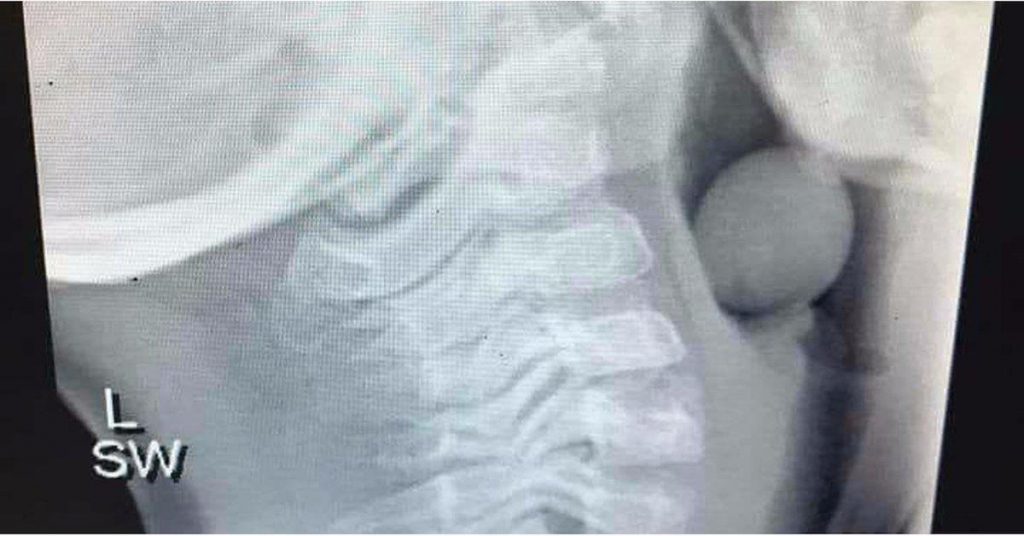

Even though grapes can be a healthy snack choice for little children, many parents don’t realize that this food can be very dangerous if it’s not cut up properly. And, not only should grapes never be served to children uncut, but it’s also important that the fruit is sliced lengthwise to prevent them from getting lodged in a child’s throat. Since the width of a grape is the same size as a small child’s airway, these snacks can easily turn deadly. And. this warning isn’t just for parents of toddlers. Angela Henderson, who is an Australian blogger, proved this point by sharing an X-ray image of a grape lodged in a 5-year-old’s throat.

“Please be mindful that not all kids chew their food, are in a rush at school to get in the playground, etc.,” Angela wrote on Facebook. “Please be careful. And when in doubt just cut the damn grapes [and] baby tomatoes.” And, according to Angela, this little boy had to be operated on under general anesthesia so that doctors to remove the grape. She also went on to explain that his mom gave her permission for the X-ray to be shared. The mother hopes that this photo will raise awareness on the issues so that no other families will make the same mistake that they did. “He is VERY lucky that part of his airway was open, or else this could have ended badly,” Angela said.